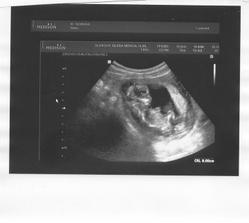

30.11. 19+0tt velký utz, Kobliha velikostně odpovídá, váží 250g, placenta vzadu nahoře, spadnul mi třetí větší kámen ze srdce